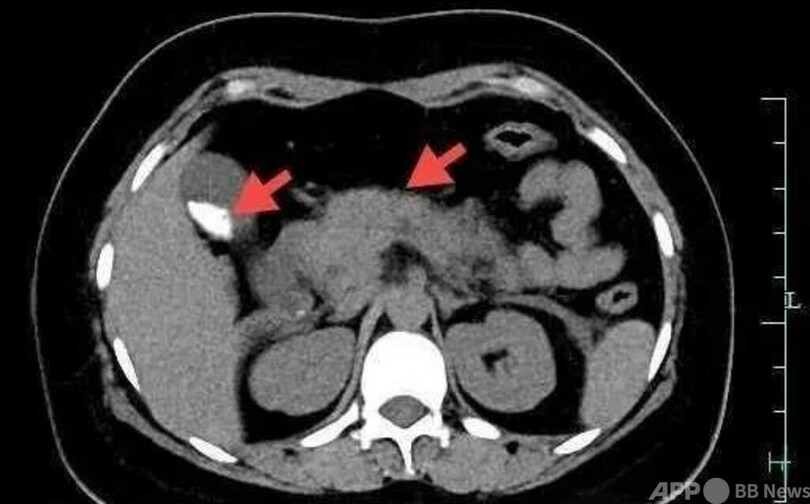

中国東部浙江省杭州市に住む25歳の女性、慧さんは、健康診断で胆のう結石を患っていると知らされました。日常何の症状もなかったため、特に気にせず過ごしていました。10月20日、両親は家で大きなカニを蒸し、仕事で忙しい娘をねぎらおうとしました。慧さんはそのカニを一気に4杯食べ、食後、上腹部にかすかな痛みを感じ始めました。「ただの食べ過ぎで、少し我慢すれば良くなる」と思いましたが、約30分後に痛みがより激しくなり、家族に杭州市中医学病院へ搬送され、救急治療を受けました。各項目の検査結果と胆のう結石の持病があることから、食べ過ぎによる急性膵炎と診断され、すぐ入院することになりました。その後、抗感染症、鎮痛、酵素抑制など一連の治療を受け、胆のう切除手術を受けました。

医師の話によりますと、胆石症、肥満、脂質異常、糖尿病などの基礎疾患を持つ人は、食べ過ぎを避けるべきです。慧さんはカニみそやカニ膏(雄カニの精液と精のう)を食べ過ぎたことで、重症急性膵炎の発作を招いたとのことです。(c)CGTN Japanese/AFPBB News